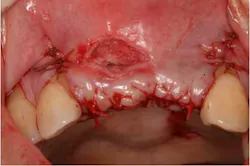

A 43-year-old female with a noncontributory medical history taking no medication and having no known food/drug allergies presented to my general dental office with a chief complaint of having “loose teeth with an underbite.” Clinically, she had generalized, moderate, chronic periodontal disease and was missing teeth Nos. 8 through 10. She had a Class III malocclusion with pathologic flaring of her remaining anterior teeth. She had both vertical and horizontal tissue loss in the No. 8 through 10 region. The patient wore a transitional partial denture to replace the anterior missing teeth that was placed in edge-to-edge occlusion by her previous dentist. (Fig. 1) She did not like having a removable prosthetic and desired a fixed option in the form of implants to replace her missing teeth. I sent her to the periodontist for a periodontal consult for her remaining dentition and dental implants to replace her missing front teeth.